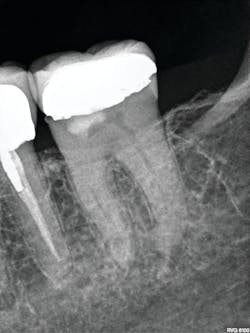

In more dense anatomic areas, more subtle radiographic findings that are not appreciated with projection radiography are visible in a passing glance with CBCT. Advanced imaging also helps with treatment planning and image-guided treatment (IGT). IGT, particularly in endodontics, allows a better estimation of the anatomic complexity and possible strategies for managing it. This also facilitates planned endodontic access to minimize the amount of sound tooth structure that is removed and maximize the remaining dentin.

In a specialty practice, we often receive referrals of asymptomatic patients with existing chronic conditions, such as long-standing periapical findings on previously treated teeth and asymptomatic resorptions discovered with screening projection radiography. Advanced imaging allows us to do active surveillance with short-term follow-ups of six months to one year. In these cases, we can evaluate for interval change to help determine if the findings are correct, and then we can adjust treatment planning accordingly. The advanced features of our CBCT system allow us to provide added services to patients and referring doctors through referral-based imaging of the TMJ, teeth, sinus, and airways (with appropriate consultation with an ENT doctor), thus saving patients an extra trip to an imaging center.